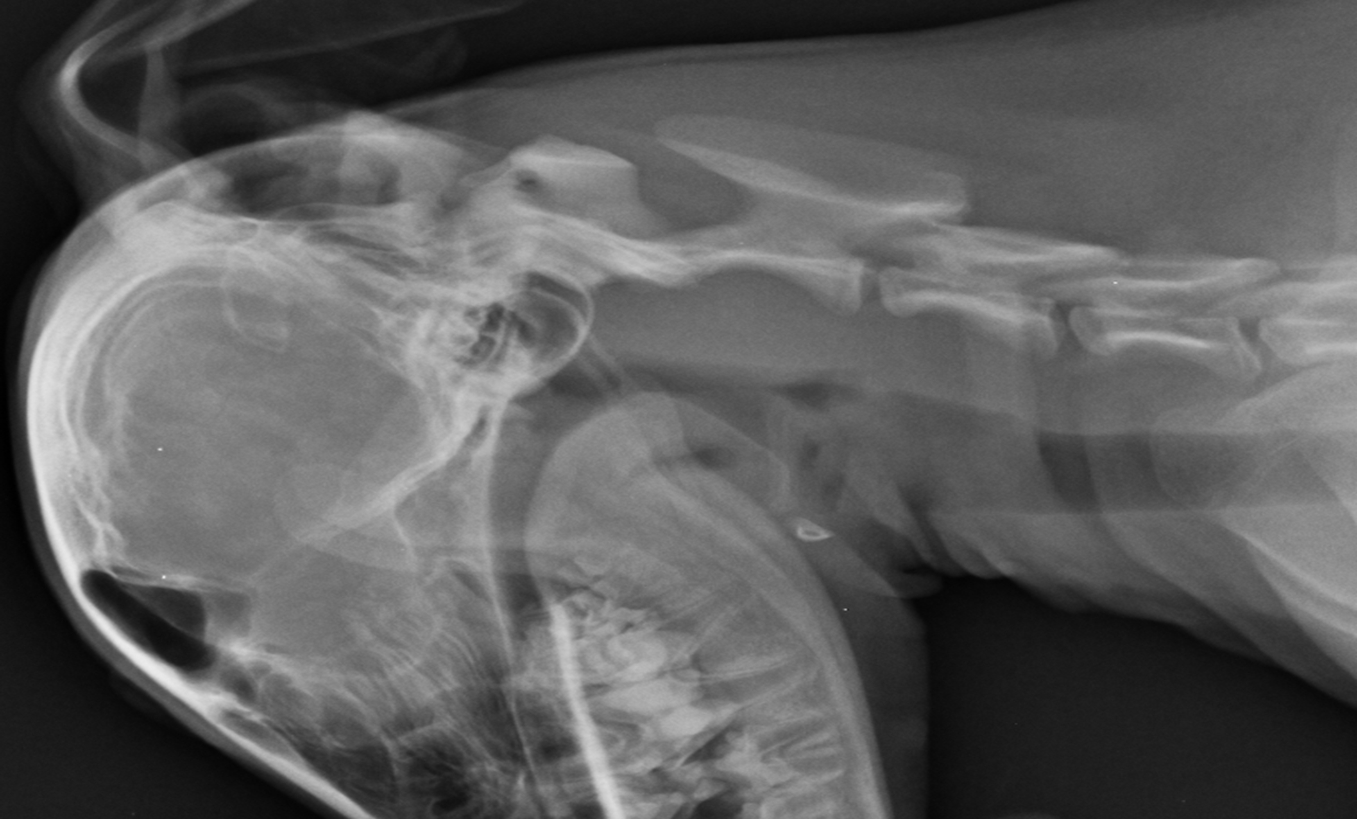

A subluxação atlantoaxial ou instabilidade atlantoaxial, é uma afecção articular onde ocorre o deslocamento dorsal do áxis (C2) em relação ao atlas (C1) levando a uma compressão da medula espinhal, podendo ser de forma congênita ou adquirida. Os cães acometidos apresentam sinais clínicos relacionados ao nervo motor superior (NMS) como consequência da compressão medular cervical, tendo curso agudo ou crônico, intermitentes ou não. O diagnóstico é realizado através da avaliação dos sinais neurológicos, exame clínico e exames de imagem. O tratamento pode ser médico, com o repouso, uso de colar cervical e utilização de analgésicos e anti-inflamatórios ou cirúrgico, visando a redução e estabilização permanente da articulação e eliminar a compressão medular. Este trabalho tem como objetivo relatar o atendimento a um canídeo, fêmea, sem raça definida, com 6 meses de idade e 6 kg, atendido no hospital veterinário do Centro Universitário Ingá, apresentando cervicalgia, relutância ao movimento de cabeça e pescoço, ataxia, quedas ao locomover-se e paresia de membros posteriores de curso agudo, tendo início a aproximadamente 2 dias tendo sido, através do exame radiográfico diagnosticada com Subluxação atlantoaxial congênita, tendo sido instituído tratamento conservativo com uso de colar cervico torácico e repouso em canil, tendo sido prescrito cloridrato de tramadol, dipirona, meloxicam e ranitidina, obtendo-se resposta satisfatória ao quadro, sem qualquer sinal recidiva durante 6 meses de acompanhamento.